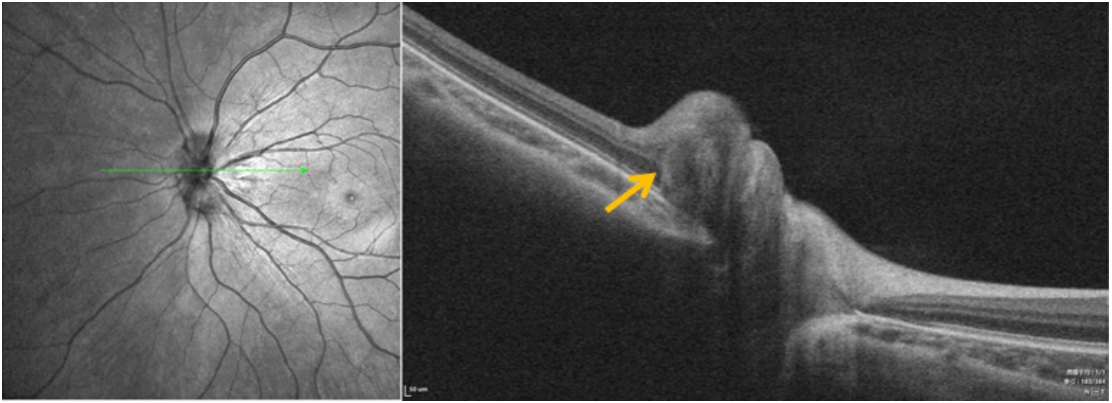

PHOMS这一名称源于通过增强深度成像光学相干断层扫描(enhanced depth imaging optical coherence tomography, EDI-OCT)成像确定的视神经盘水平B扫描(横截面)的形态学描述,其特征是位于视盘旁、Bruch膜开口(bruch's membrane opening, BMO)两侧、Bruch膜/RPE复合体上方、内部呈现均匀的高反射信号,其反射率与视网膜神经纤维层和神经节细胞层相似[29-30]。研究发现,视盘倾斜度增加与 PHOMS 有关[31-33]。2014 年的一项研究称39.5% 的TDS儿童患者有“圆顶状高反射结构”,红外图像显示视盘边缘鼻侧隆起,与神经倾斜插入一致[18]。Kim等[34]也报道了2例被诊断患有PHOMS患者在随访过程中逐渐出现了视盘倾斜。这可能是由于在TDS中筛板相对于BMO的鼻侧位移以及巩膜和筛板的逐渐拉伸,导致视神经轴突穿过筛板孔隙时引起局部应力,尤其是在鼻侧视盘的纤维中。这种异常形态容易导致慢性轴浆淤滞,进而在鼻侧形成可识别的 S 形视盘周围膨大,导致鼻侧假性视盘水肿和视盘隆起,在检眼镜和OCT上可识别为特征性的“C”形光晕(图5、6)。持续的神经纤维弯曲和轴浆流障碍可能造成损伤,对造成视野不可矫正的损害。

图 5 TDS合并PHOMS患者眼底照片

Figure 5 Fundus photos of patients with TDS combined with PHOMS

图 6 TDS合并PHOMS患者OCT成像,PHOMS(黄色箭头) Figure 6 OCT imaging of patients with TDS combined with PHOMS, PHOMS (yellow arrow)